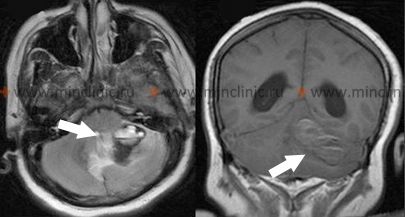

- Structural Vascular Lesions: Such as Arteriovenous Malformations (AVMs) or Cavernous Malformations (cavernomas). These are more frequent causes in younger patients [1, 4].

| Cavernous Malformation (Cavernoma) | Can occur at any age. Often smaller bleeds, may be recurrent. Can present with seizures or focal deficits without overt hemorrhage. Familial forms exist. | MRI: Characteristic "popcorn" lesion with mixed signal, hemosiderin rim. Angiographically occult. |

| Hemorrhage into Tumor (Primary or Metastatic) | Bleeding within a pre-existing mass. May have prior progressive neurological symptoms. Certain tumor types predispose (melanoma, RCC, chorio, GBM). | MRI with contrast: Shows hematoma associated with enhancing tumor mass, often significant surrounding edema. History of primary cancer (for mets). |